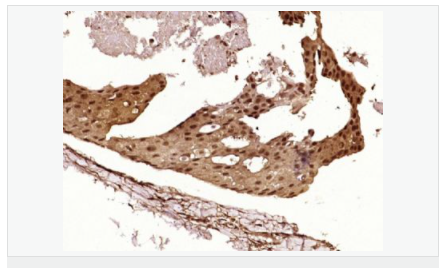

| 產(chǎn)品應(yīng)用 | WB=1:500-2000 ELISA=1:5000-10000 IHC-P=1:100-500 IHC-F=1:100-500 Flow-Cyt=1μg/Test ICC=1:100 IF=1:100-500 (石蠟切片需做抗原修復(fù)) not yet tested in other applications. optimal dilutions/concentrations should be determined by the end user. |

| 細(xì)胞定位 | 細(xì)胞核 細(xì)胞漿 |

| 產(chǎn)品介紹 | This gene encodes a tumor suppressor protein containing transcriptional activation, DNA binding, and oligomerization domains. The encoded protein responds to diverse cellular stresses to regulate expression of target genes, thereby inducing cell cycle arrest, apoptosis, senescence, DNA repair, or changes in metabolism. Mutations in this gene are associated with a variety of human cancers, including hereditary cancers such as Li-Fraumeni syndrome. Alternative splicing of this gene and the use of alternate promoters result in multiple transcript variants and isoforms. Additional isoforms have also been shown to result from the use of alternate translation initiation codons (PMIDs: 12032546, 20937277). [provided by RefSeq, Feb 2013]. Function: Acts as a tumor suppressor in many tumor types; induces growth arrest or apoptosis depending on the physiological circumstances and cell type. Involved in cell cycle regulation as a trans-activator that acts to negatively regulate cell division by controlling a set of genes required for this process. One of the activated genes is an inhibitor of cyclin-dependent kinases. Apoptosis induction seems to be mediated either by stimulation of BAX and FAS antigen expression, or by repression of Bcl-2 expression. Implicated in Notch signaling cross-over. Prevents CDK7 kinase activity when associated to CAK complex in response to DNA damage, thus stopping cell cycle progression. Isoform 2 enhances the transactivation activity of isoform 1 from some but not all TP53-inducible promoters. Isoform 4 suppresses transactivation activity and impairs growth suppression mediated by isoform 1. Isoform 7 inhibits isoform 1-mediated apoptosis. Subunit: Interacts with AXIN1. Probably part of a complex consisting of TP53, HIPK2 and AXIN1 (By similarity). Binds DNA as a homotetramer. Interacts with histone acetyltransferases EP300 and methyltransferases HRMT1L2 and CARM1, and recruits them to promoters. In vitro, the interaction of TP53 with cancer-associated/HPV (E6) viral proteins leads to ubiquitination and degradation of TP53 giving a possible model for cell growth regulation. This complex formation requires an additional factor, E6-AP, which stably associates with TP53 in the presence of E6. Interacts (via C-terminus) with TAF1; when TAF1 is part of the TFIID complex. Interacts with ING4; this interaction may be indirect. Found in a complex with CABLES1 and TP73. Interacts with HIPK1, HIPK2, and TP53INP1. Interacts with WWOX. May interact with HCV core protein. Interacts with USP7 and SYVN1. Interacts with HSP90AB1. Interacts with CHD8; leading to recruit histone H1 and prevent transactivation activity (By similarity). Interacts with ARMC10, BANP, CDKN2AIP, NUAK1, STK11/LKB1, UHRF2 and E4F1. Interacts with YWHAZ; the interaction enhances TP53 transcriptional activity. Phosphorylation of YWHAZ on 'Ser-58' inhibits this interaction. Interacts (via DNA-binding domain) with MAML1 (via N-terminus). Interacts with MKRN1. Interacts with PML (via C-terminus). Interacts with MDM2; leading to ubiquitination and proteasomal degradation of TP53. Directly interacts with FBXO42; leading to ubiquitination and degradation of TP53. Interacts (phosphorylated at Ser-15 by ATM) with the phosphatase PP2A-PPP2R5C holoenzyme; regulates stress-induced TP53-dependent inhibition of cell proliferation. Interacts with PPP2R2A. Interacts with AURKA, DAXX, BRD7 and TRIM24. Interacts (when monomethylated at Lys-382) with L3MBTL1. Isoform 1 interacts with isoform 2 and with isoform 4. Interacts with GRK5. Binds to the CAK complex (CDK7, cyclin H and MAT1) in response to DNA damage. Interacts with CDK5 in neurons. Interacts with AURKB, UHRF2 and NOC2L. Interacts (via N-terminus) with PTK2/FAK1; this promotes ubiquitination by MDM2. Interacts with PTK2B/PYK2; this promotes ubiquitination by MDM2. Interacts with PRKCG. Interacts with human cytomegalovirus/HHV-5 protein UL123. Subcellular Location: Cytoplasm. Nucleus. Nucleus, PML body. Endoplasmic reticulum. Note=Interaction with BANP promotes nuclear localization. Recruited into PML bodies together with CHEK2. Isoform 1: Nucleus. Cytoplasm. Note=Predominantly nuclear but localizes to the cytoplasm when expressed with isoform 4. Isoform 2: Nucleus. Cytoplasm. Note=Localized mainly in the nucleus with minor staining in the cytoplasm. Isoform 3: Nucleus. Cytoplasm. Note=Localized in the nucleus in most cells but found in the cytoplasm in some cells. Isoform 4: Nucleus. Cytoplasm. Note=Predominantly nuclear but translocates to the cytoplasm following cell stress. Isoform 7: Nucleus. Cytoplasm. Note=Localized mainly in the nucleus with minor staining in the cytoplasm. Isoform 8: Nucleus. Cytoplasm. Note=Localized in both nucleus and cytoplasm in most cells. In some cells, forms foci in the nucleus that are different from nucleoli. Isoform 9: Cytoplasm. Tissue Specificity: Ubiquitous. Isoforms are expressed in a wide range of normal tissues but in a tissue-dependent manner. Isoform 2 is expressed in most normal tissues but is not detected in brain, lung, prostate, muscle, fetal brain, spinal cord and fetal liver. Isoform 3 is expressed in most normal tissues but is not detected in lung, spleen, testis, fetal brain, spinal cord and fetal liver. Isoform 7 is expressed in most normal tissues but is not detected in prostate, uterus, skeletal muscle and breast. Isoform 8 is detected only in colon, bone marrow, testis, fetal brain and intestine. Isoform 9 is expressed in most normal tissues but is not detected in brain, heart, lung, fetal liver, salivary gland, breast or intestine. Post-translational modifications: Acetylated. Acetylation of Lys-382 by CREBBP enhances transcriptional activity. Deacetylation of Lys-382 by SIRT1 impairs its ability to induce proapoptotic program and modulate cell senescence. Phosphorylation on Ser residues mediates transcriptional activation. Phosphorylated by HIPK1. Phosphorylation at Ser-9 by HIPK4 increases repression activity on BIRC5 promoter. Phosphorylated on Thr-18 by VRK1. Phosphorylated on Ser-20 by CHEK2 in response to DNA damage, which prevents ubiquitination by MDM2. Phosphorylated on Ser-20 by PLK3 in response to reactive oxygen species (ROS), promoting p53/TP53-mediated apoptosis. Phosphorylated on Thr-55 by TAF1, which promotes MDM2-mediated degradation. Phosphorylated on Ser-33 by CDK7 in a CAK complex in response to DNA damage. Phosphorylated on Ser-46 by HIPK2 upon UV irradiation. Phosphorylation on Ser-46 is required for acetylation by CREBBP. Phosphorylated on Ser-392 following UV but not gamma irradiation. Phosphorylated upon DNA damage, probably by ATM or ATR. Phosphorylated on Ser-15 upon ultraviolet irradiation; which is enhanced by interaction with BANP. Phosphorylated by NUAK1 at Ser-15 and Ser-392; was initially thought to be mediated by STK11/LKB1 but it was later shown that it is indirect and that STK11/LKB1-dependent phosphorylation is probably mediated by downstream NUAK1 (PubMed:21317932). It is unclear whether AMP directly mediates phosphorylation at Ser-15. Phosphorylated on Thr-18 by isoform 1 and isoform 2 of VRK2. Phosphorylation on Thr-18 by isoform 2 of VRK2 results in a reduction in ubiquitination by MDM2 and an increase in acetylation by EP300. Stabilized by CDK5-mediated phosphorylation in response to genotoxic and oxidative stresses at Ser-15, Ser-33 and Ser-46, leading to accumulation of p53/TP53, particularly in the nucleus, thus inducing the transactivation of p53/TP53 target genes. Phosphorylated at Ser-315 and Ser-392 by CDK2 in response to DNA-damage. Dephosphorylated by PP2A-PPP2R5C holoenzyme at Thr-55. SV40 small T antigen inhibits the dephosphorylation by the AC form of PP2A. May be O-glycosylated in the C-terminal basic region. Studied in EB-1 cell line. Ubiquitinated by MDM2 and SYVN1, which leads to proteasomal degradation. Ubiquitinated by RFWD3, which works in cooperation with MDM2 and may catalyze the formation of short polyubiquitin chains on p53/TP53 that are not targeted to the proteasome. Ubiquitinated by MKRN1 at Lys-291 and Lys-292, which leads to proteasomal degradation. Deubiquitinated by USP10, leading to its stabilization. Ubiquitinated by TRIM24, which leads to proteasomal degradation. Ubiquitination by TOPORS induces degradation. Deubiquitination by USP7, leading to stabilization. Isoform 4 is monoubiquitinated in an MDM2-independent manner. Monomethylated at Lys-372 by SETD7, leading to stabilization and increased transcriptional activation. Monomethylated at Lys-370 by SMYD2, leading to decreased DNA-binding activity and subsequent transcriptional regulation activity. Lys-372 monomethylation prevents interaction with SMYD2 and subsequent monomethylation at Lys-370. Dimethylated at Lys-373 by EHMT1 and EHMT2. Monomethylated at Lys-382 by SETD8, promoting interaction with L3MBTL1 and leading to repress transcriptional activity. Demethylation of dimethylated Lys-370 by KDM1A prevents interaction with TP53BP1 and represses TP53-mediated transcriptional activation. Sumoylated by SUMO1. DISEASE: Note=TP53 is found in increased amounts in a wide variety of transformed cells. TP53 is frequently mutated or inactivated in about 60% of cancers. TP53 defects are found in Barrett metaplasia a condition in which the normally stratified squamous epithelium of the lower esophagus is replaced by a metaplastic columnar epithelium. The condition develops as a complication in approximately 10% of patients with chronic gastroesophageal reflux disease and predisposes to the development of esophageal adenocarcinoma. Defects in TP53 are a cause of esophageal cancer (ESCR) [MIM:133239]. Defects in TP53 are a cause of Li-Fraumeni syndrome (LFS) [MIM:151623]. LFS is an autosomal dominant familial cancer syndrome that in its classic form is defined by the existence of a proband affected by a sarcoma before 45 years with a first degree relative affected by any tumor before 45 years and another first degree relative with any tumor before 45 years or a sarcoma at any age. Other clinical definitions for LFS have been proposed (PubMed:8118819 and PubMed:8718514) and called Li-Fraumeni like syndrome (LFL). In these families affected relatives develop a diverse set of malignancies at unusually early ages. Four types of cancers account for 80% of tumors occurring in TP53 germline mutation carriers: breast cancers, soft tissue and bone sarcomas, brain tumors (astrocytomas) and adrenocortical carcinomas. Less frequent tumors include choroid plexus carcinoma or papilloma before the age of 15, rhabdomyosarcoma before the age of 5, leukemia, Wilms tumor, malignant phyllodes tumor, colorectal and gastric cancers. Defects in TP53 are involved in head and neck squamous cell carcinomas (HNSCC) Defects in TP53 are a cause of lung cancer (LNCR) [MIM:211980]. LNCR is a common malignancy affecting tissues of the lung. The most common form of lung cancer is non-small cell lung cancer (NSCLC) that can be divided into 3 major histologic subtypes: squamous cell carcinoma, adenocarcinoma, and large cell lung cancer. NSCLC is often diagnosed at an advanced stage and has a poor prognosis. Defects in TP53 are a cause of choroid plexus papilloma (CPLPA) [MIM:260500]. Choroid plexus papilloma is a slow-growing benign tumor of the choroid plexus that often invades the leptomeninges. In children it is usually in a lateral ventricle but in adults it is more often in the fourth ventricle. Hydrocephalus is common, either from obstruction or from tumor secretion of cerebrospinal fluid. If it undergoes malignant transformation it is called a choroid plexus carcinoma. Primary choroid plexus tumors are rare and usually occur in early childhood. Defects in TP53 are a cause of adrenocortical carcinoma (ADCC) [MIM:202300]. ADCC is a rare childhood tumor of the adrenal cortex. It occurs with increased frequency in patients with the Beckwith-Wiedemann syndrome and is a component tumor in Li-Fraumeni yndrome. Similarity: Belongs to the p53 family. SWISS: P04637 Gene ID: 7157 Database links: Entrez Gene: 7157 Human Entrez Gene: 22059 Mouse Omim: 191170 Human SwissProt: P04637 Human SwissProt: P02340 Mouse Unigene: 654481 Human Unigene: 222 Mouse Unigene: 54443 Rat Important Note: This product as supplied is intended for research use only, not for use in human, therapeutic or diagnostic applications. wtp53廣泛的研究發(fā)現(xiàn)P53腫瘤抑制基因?qū)?0%以上的人類癌癥具有抑制突變的功能。P53蛋白水平在正常細(xì)胞中表達(dá)低,在DNA突變時或各種各樣細(xì)胞遇難信號時反應(yīng)增加。該基因突變或缺失是導(dǎo)致許多腫瘤發(fā)生的原因。 野生型P53(wt-p53)可誘導(dǎo)細(xì)胞凋亡,并通過細(xì)胞凋亡抑制腫瘤生長,而P53的突變或缺失則可抑制野生型P53的功能,使得缺陷細(xì)胞得以存活下來,從而導(dǎo)致腫瘤發(fā)生。 P53同時也是細(xì)胞凋亡的調(diào)控因子。此抗體可用于P53腫瘤抑制基因功能的研究。 |